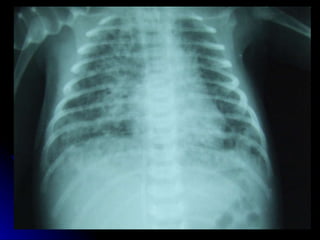

Hyaline membrane disease Clinical:- Usually preterm Tachypnoea > 60 Indrawing/ retraction/ recession Grunting Nasal flaring Cyanosis in air Presents within a few hours of life

HMD - Aetiology Surfactant deficiency Structurally immature lungs

HMD - Treatment Oxygen CPAP Mechanical ventilation Surfactant replacement

Hyaline membrane diseaseClinical:- Usually preterm Tachypnoea > 60 Indrawing/ retraction/ recession Grunting Nasal flaring Cyanosis in air Presents within a few hours of life

HMD - AetiologySurfactant deficiency Structurally immature lungs

HMD - TreatmentOxygen CPAP Mechanical ventilation Surfactant replacement